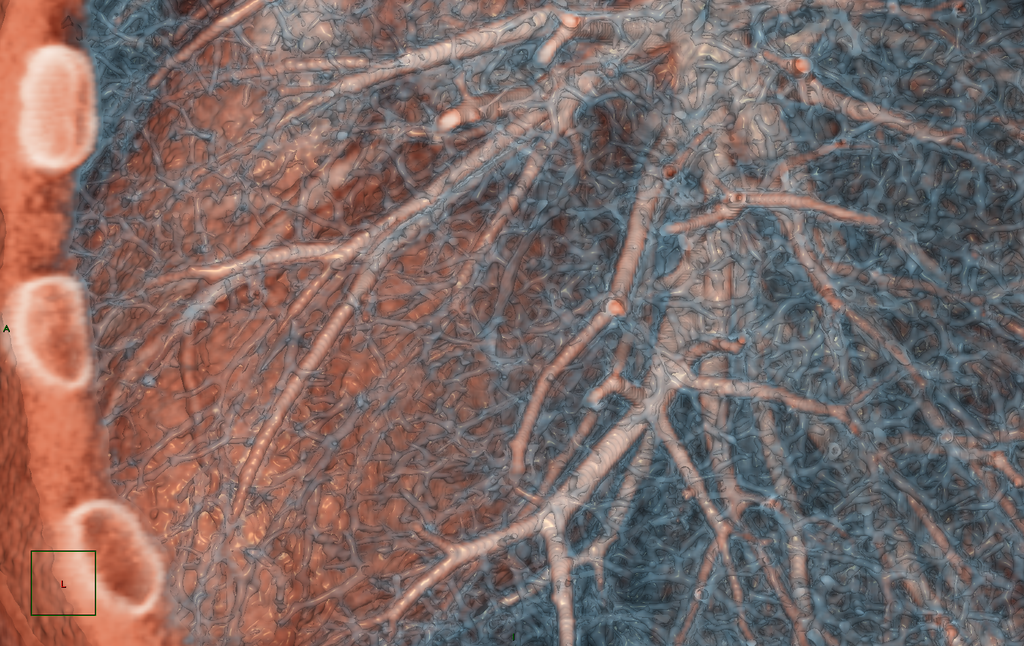

Vías aéreas. Bronquios y bronquiolos de un pulmón humano, nótese el gran entramado de ramificaciones por las cuales viaja el aire que inhalamos, al final del recorrido encontramos a los alveolos, pequeñas bolsas donde la sangre recoge el oxígeno y entrega el bióxido de carbono, mediante un complejo proceso de difusión entre gas y líquido. TC con reconstrucción en 3D. Credito nuevamente a voxel123 de deviantart